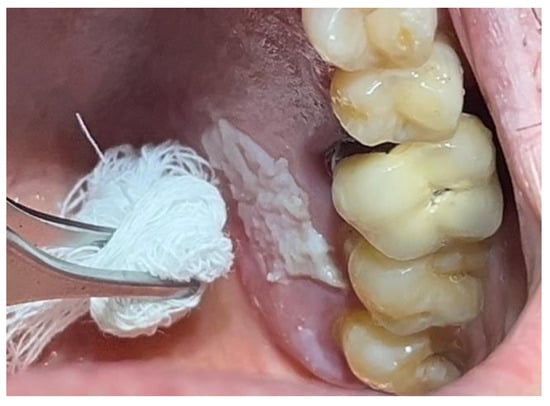

In a 49-year-old patient with ischemic heart disease, Glubran II was used as a stabilizing material for natural bone graft granules at a site rehabilitated with implant-prosthetic treatment, with the aim of achieving volumetric enhancement of the buccal bone. Following specific guidelines for surgical treatment of ischemic heart disease (4), implant therapy was carried out (Figure 8). Natural bone graft material (Bio-Oss®—Geistlich, Baden-Baden, Germany) was applied and stabilized with Glubran II. The application was made using an endodontic needle, depositing single droplets of the glue to cover the entire graft material before placing the prepared flap on top (Figure 9). This technique achieved stable graft fixation at the recipient site, demonstrating the efficacy of Glubran II for internal use (Figure 10).

During the postoperative period, no complications were reported, and no signs of material rejection or inflammation at the surgical site occurred. The site was sutured with absorbable sutures (Ethicon Vicryl Rapid 4/0, Johnson & Johnson, New Brunswick, NJ, USA), and soft tissue healing was completed within 15–20 days. A proper evaluation of graft integration and potential bone regeneration will require 3–4 months, but the current results show Glubran II’s effectiveness in stabilizing the graft and preventing inflammation, both in the bone and soft tissue, making it a valuable tool for socket preservation techniques.

Figure 4. Hemostasis control at the surgical site following excision of the lesion with Glubran II using an endodontic needle.

Figure 9. Stabilization of bone regeneration material with Glubran II.

Materials 18 02642 g009

Figure 10. Surgical site at the end of the polymerization time of Glubran II; the site was subjected to tensile testing, with positive results under the applied tensions.

Materials 18 02642 g010